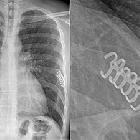

Rippenklammern

Osteosynthese

bei instabilem Thorax bei Rippenserienfraktur mit Rippenklammern.

Rekonstruktion

instabile Brustwand Rippenklammern. Neben den versorgten Rippenfrakturen beidseits weitere weniger verschobene Frakturen.